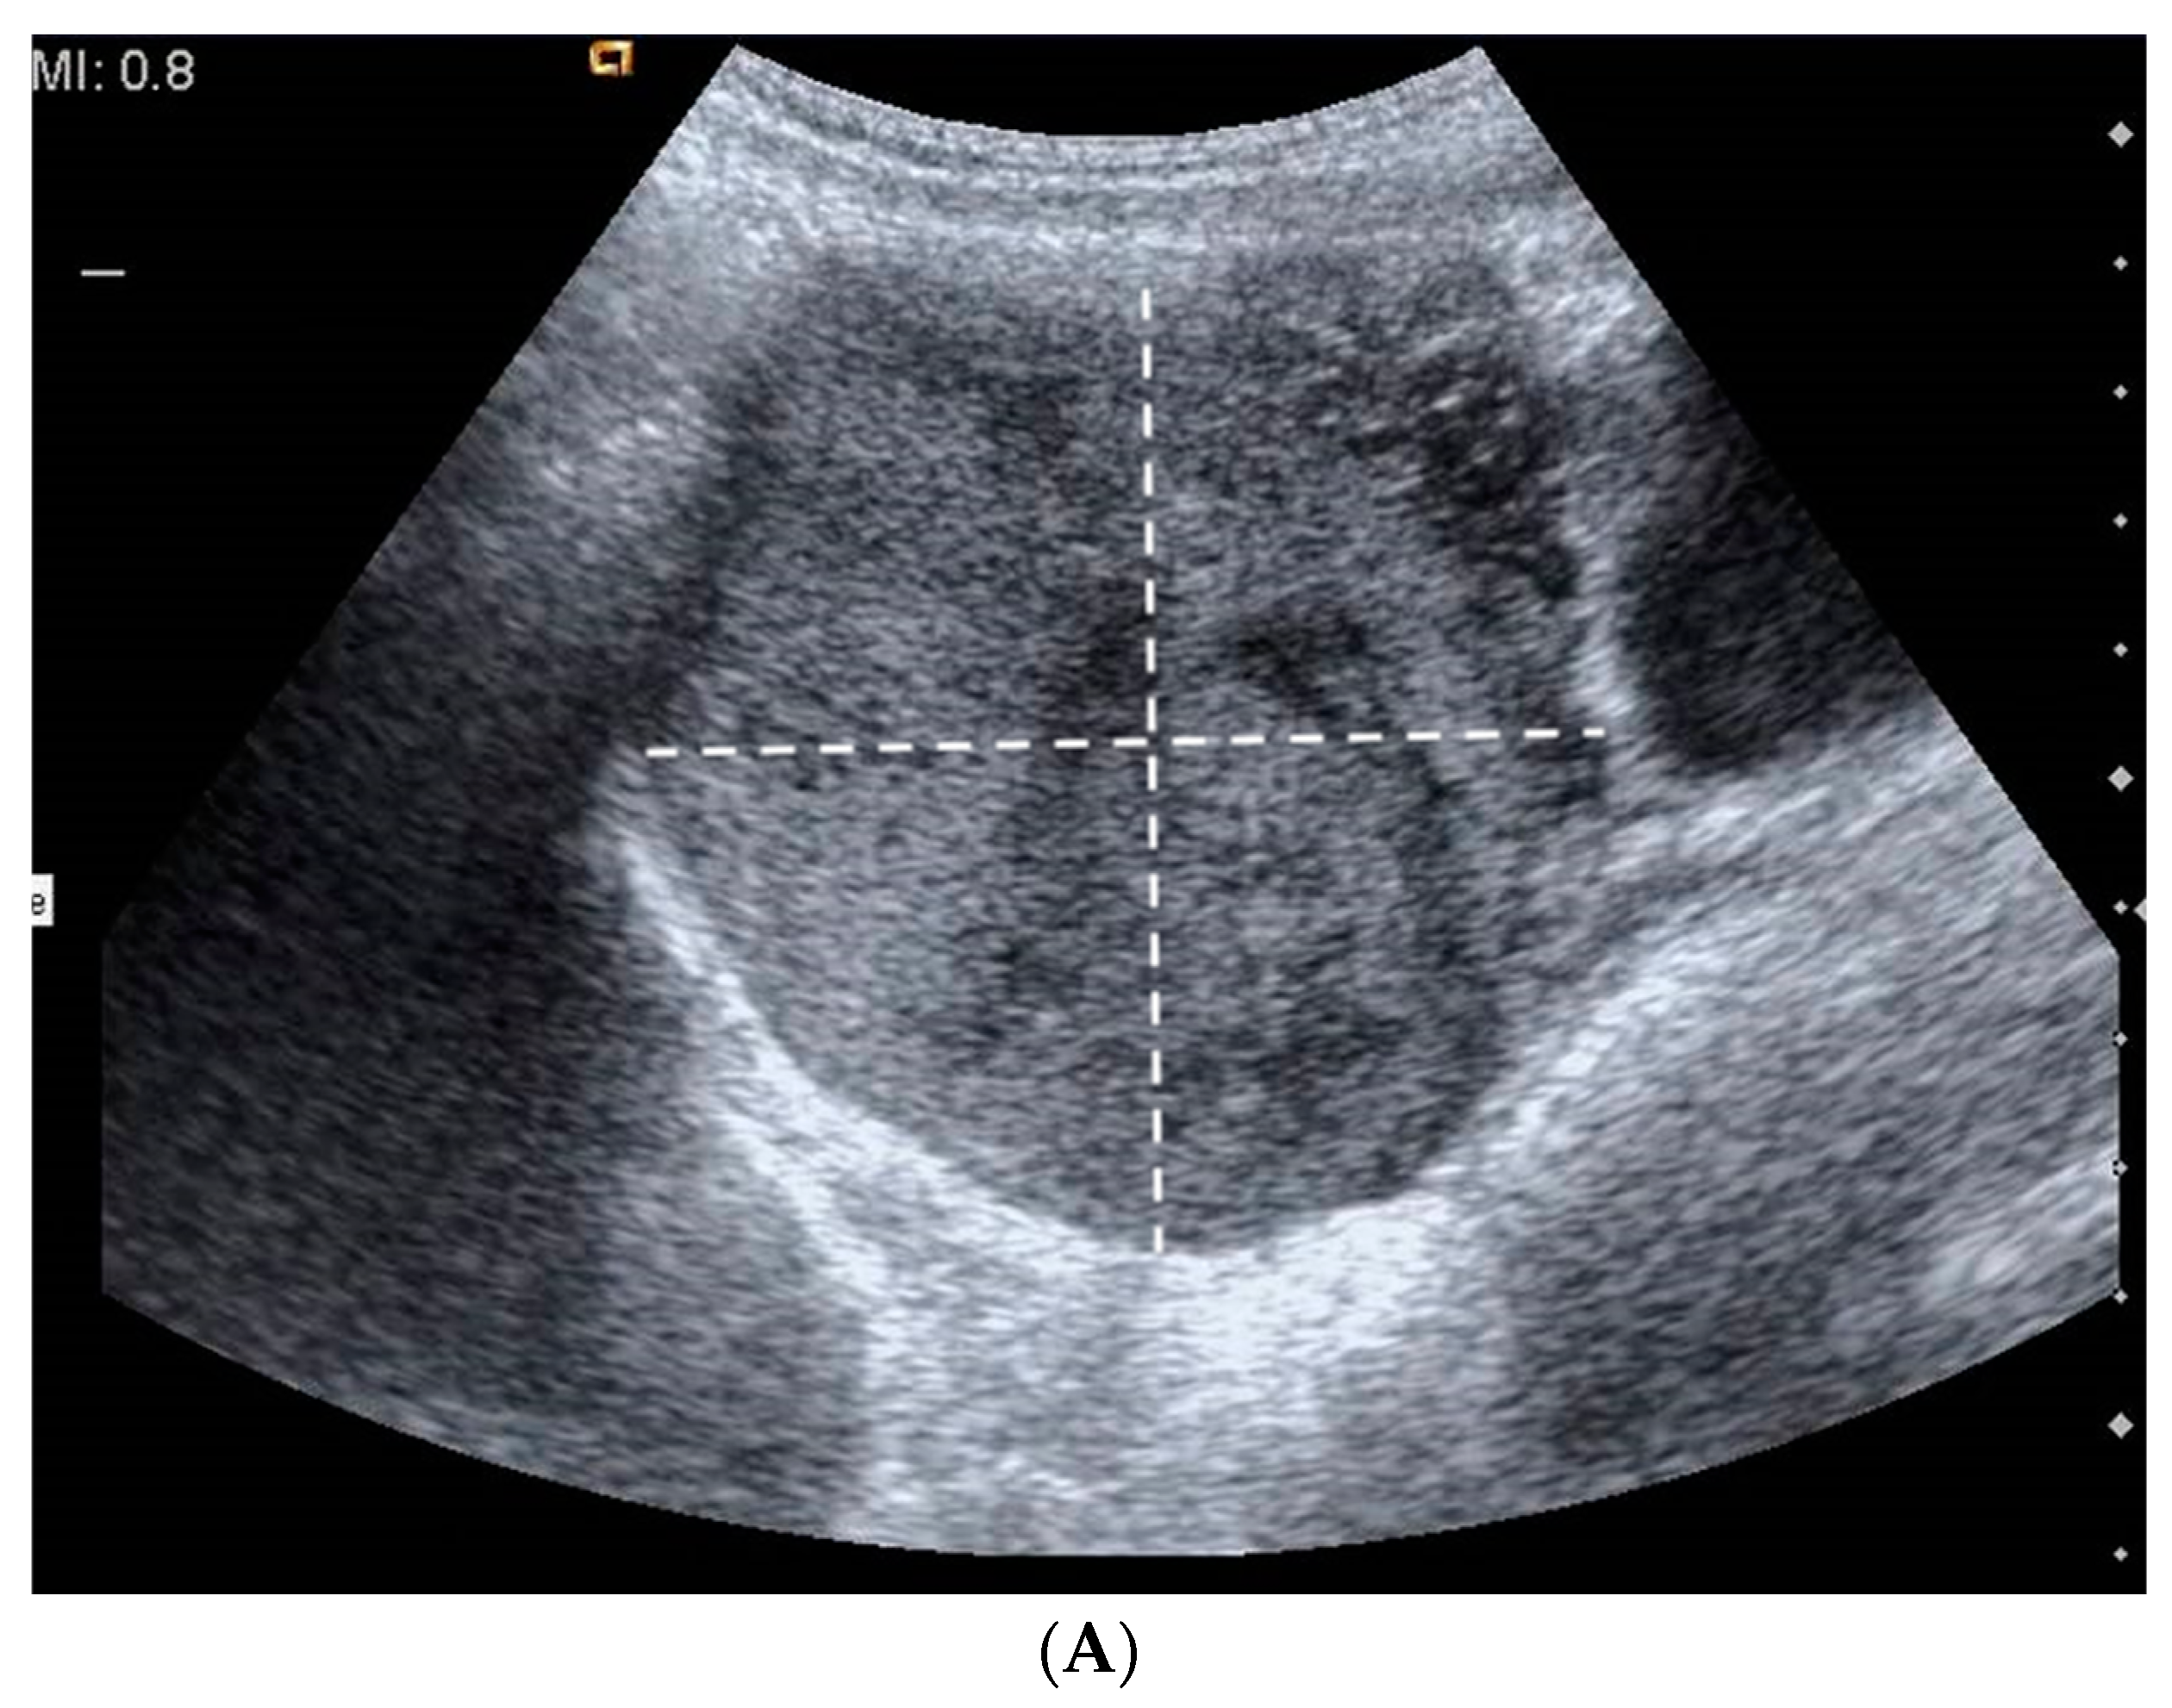

3.1. Case 1

3.2. Case 2

3.3. Case 3